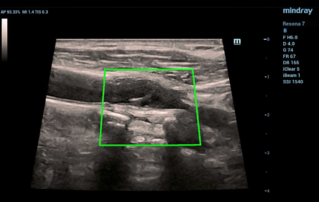

Female pelvic floor anatomy, which developed since the early 20th century, has had a variety of theories, including integral theory, three levels of vaginal support theory, "hammock hypothesis", and three-chamber system. Supporting structures such as pelvic floor muscles, fascia and ligament play an important role in maintaining the normal function of pelvic floor, among which levator ani muscle group is one of the most important supporting structures.